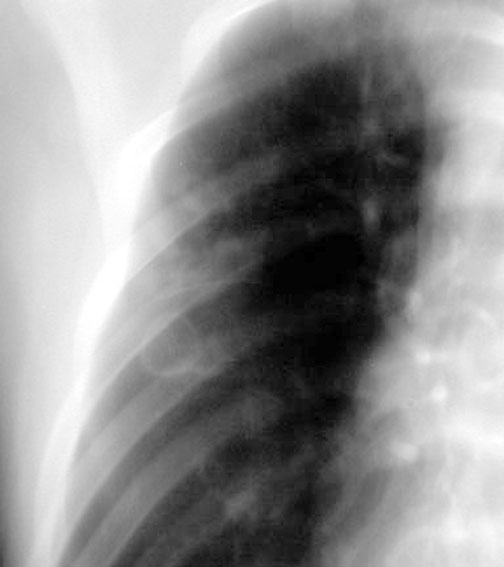

Case 4

Lateral